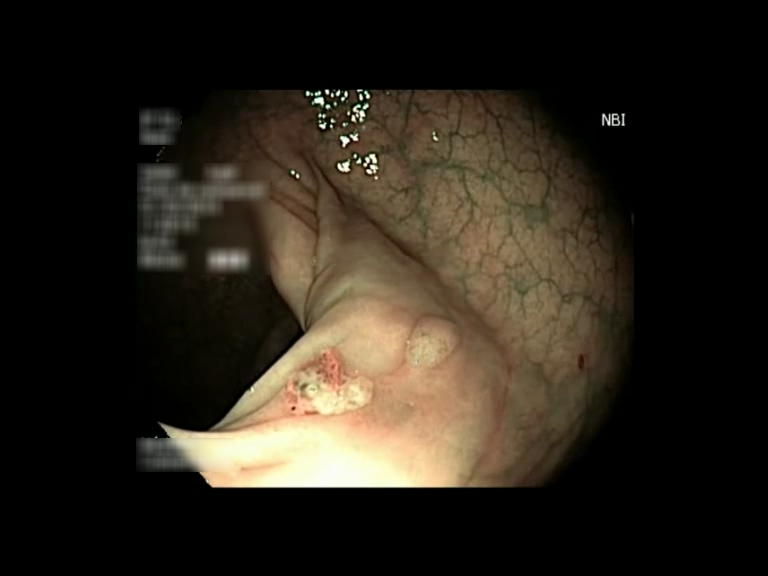

| Lesion | White Light Frame | NBI Frame | White Light Video | NBI Video | Camera Calibration |

| hyperplasic_01 |  |

|

WL.mp4 | NBI.mp4 | cam.xml |